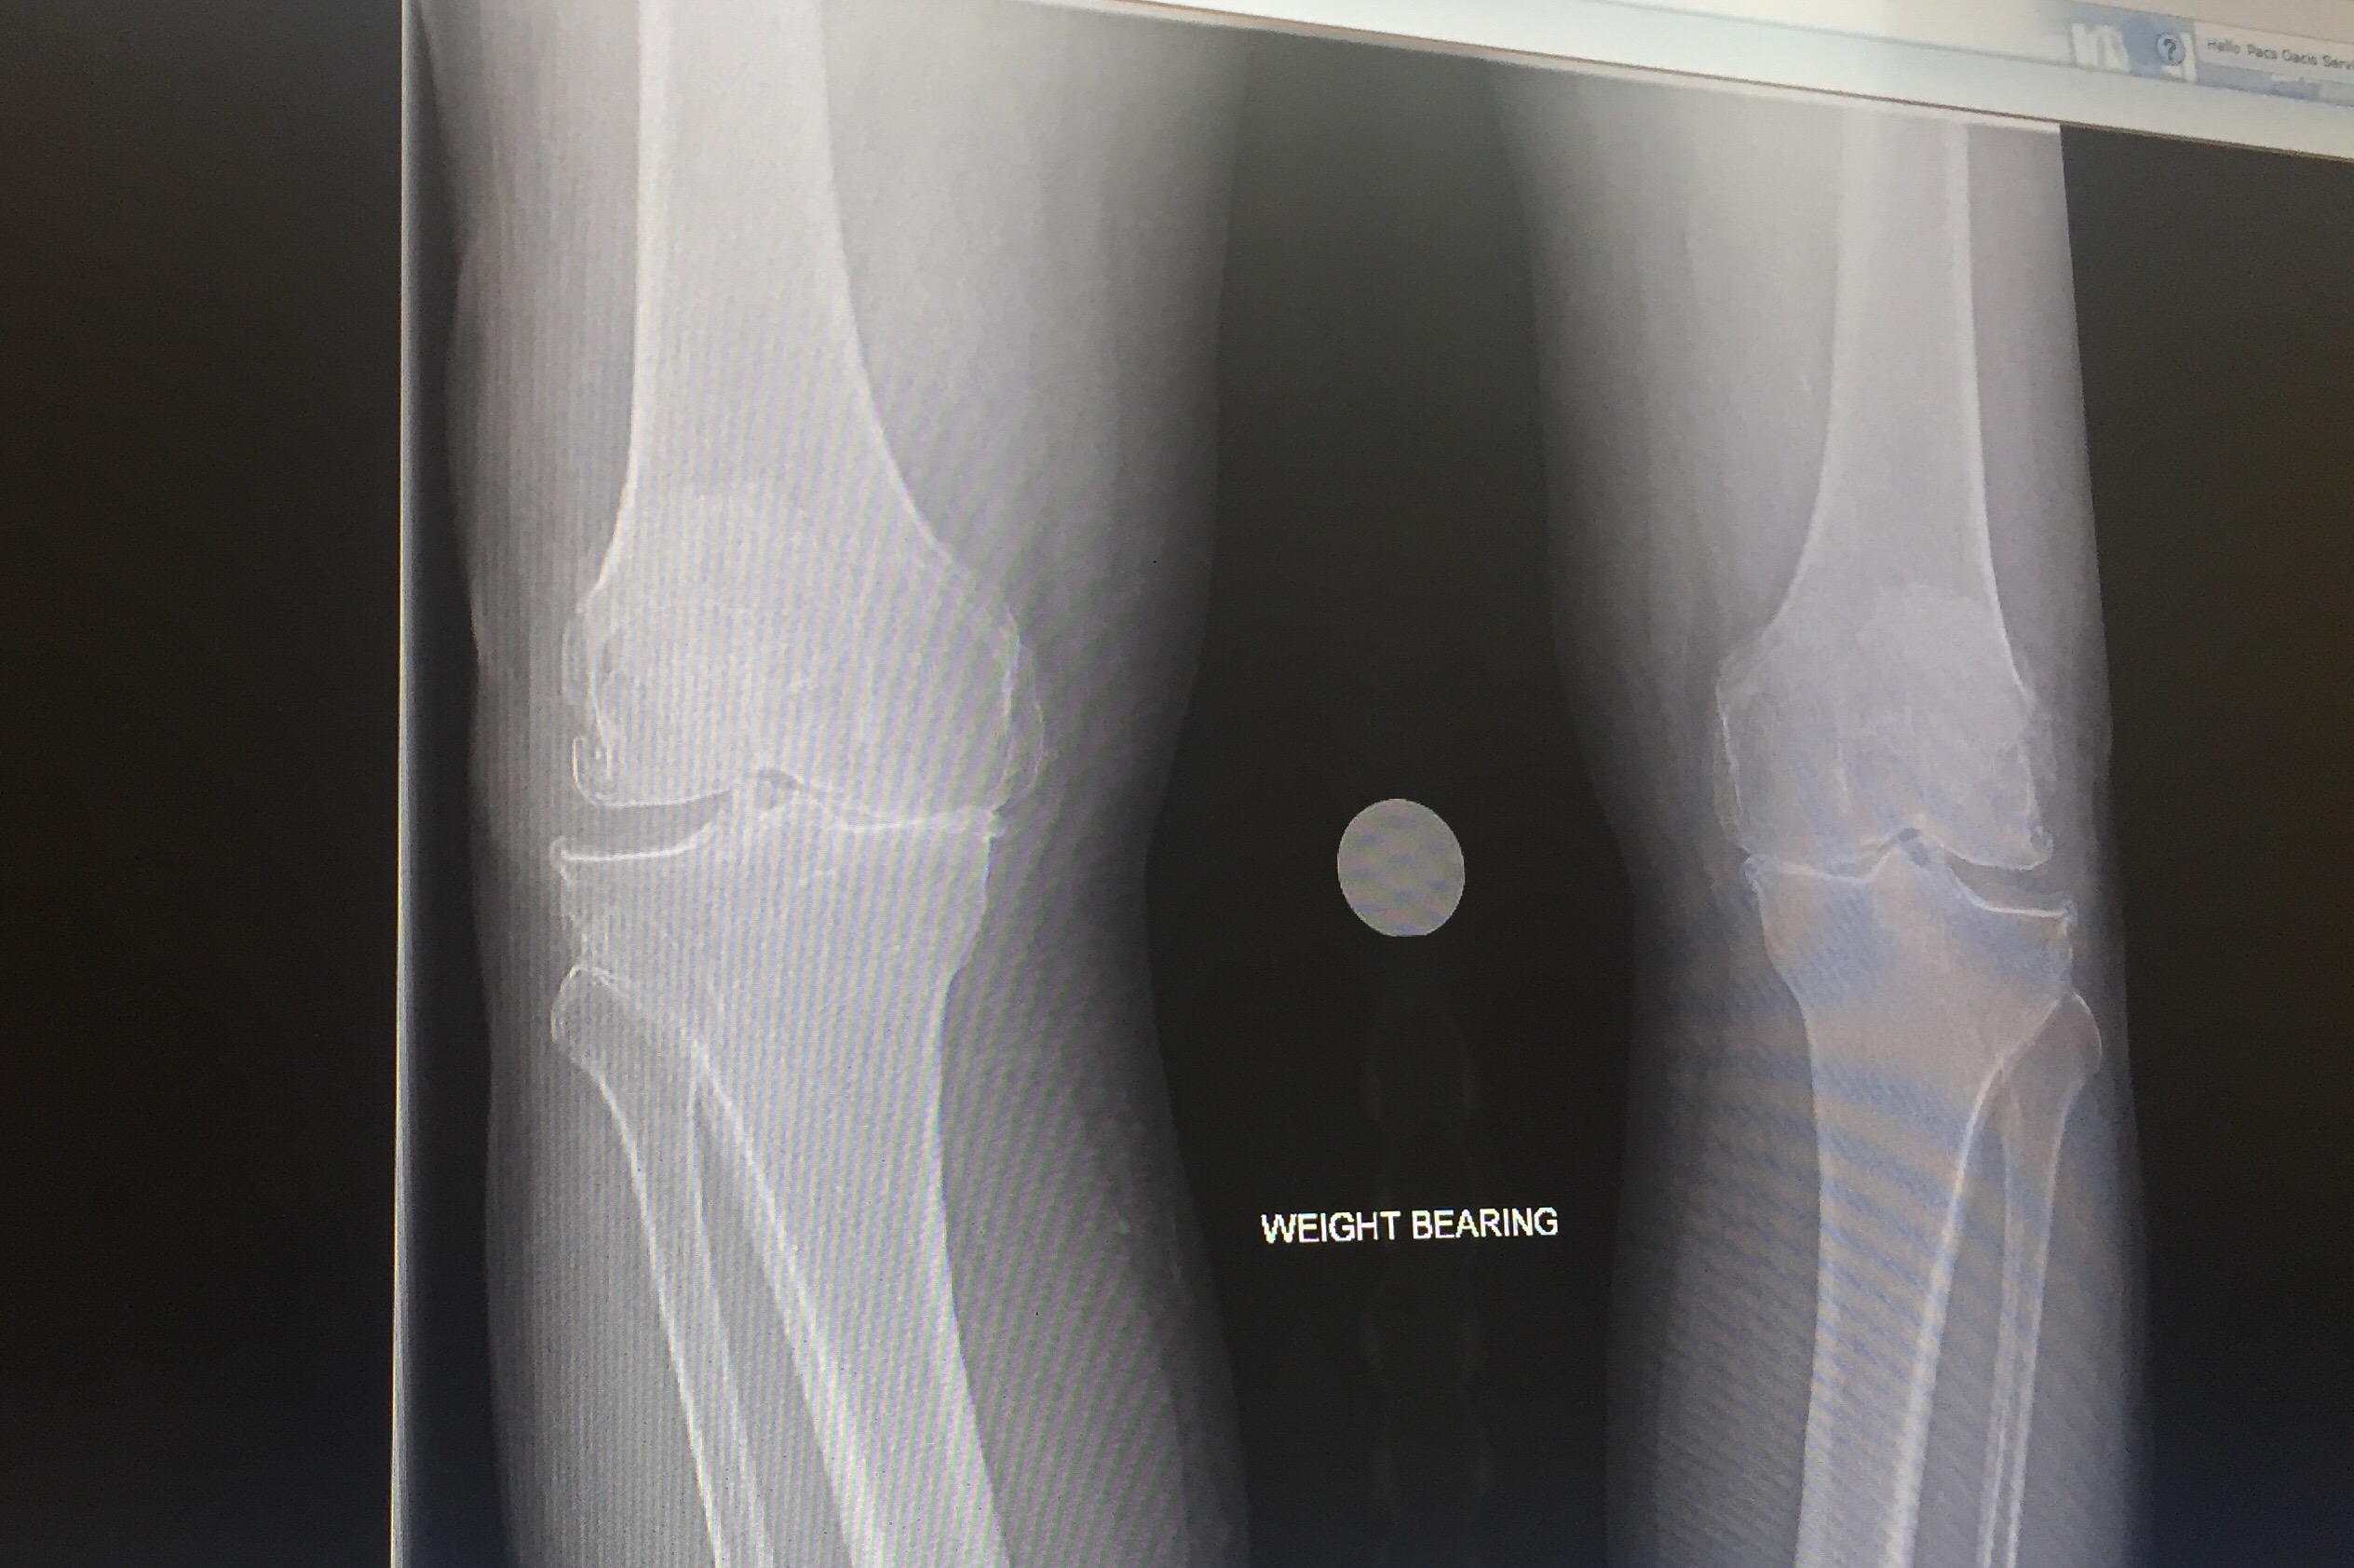

Graeme, my physio went onto his computer and showed me the results from the MRI I had at Flinders, and the Pet scan I had at the Royal Adelaide Hospital.

He read me the notes that were attached to each photo from the MRI and the Pet Scan, and I was able to photograph the MRI and the Pet Scan from the screen onto my iPhone.

This of course means that it is entirely possible that if I should need to have (as I do) another knee replacement, then the same thing could happen again, and I could have another stroke as a result of another knee replacement operation.

My left knee, the un-operated on knee, has rapidly become my “bad” knee, and so, unfortunately, such an operation is definitely “on the cards.”